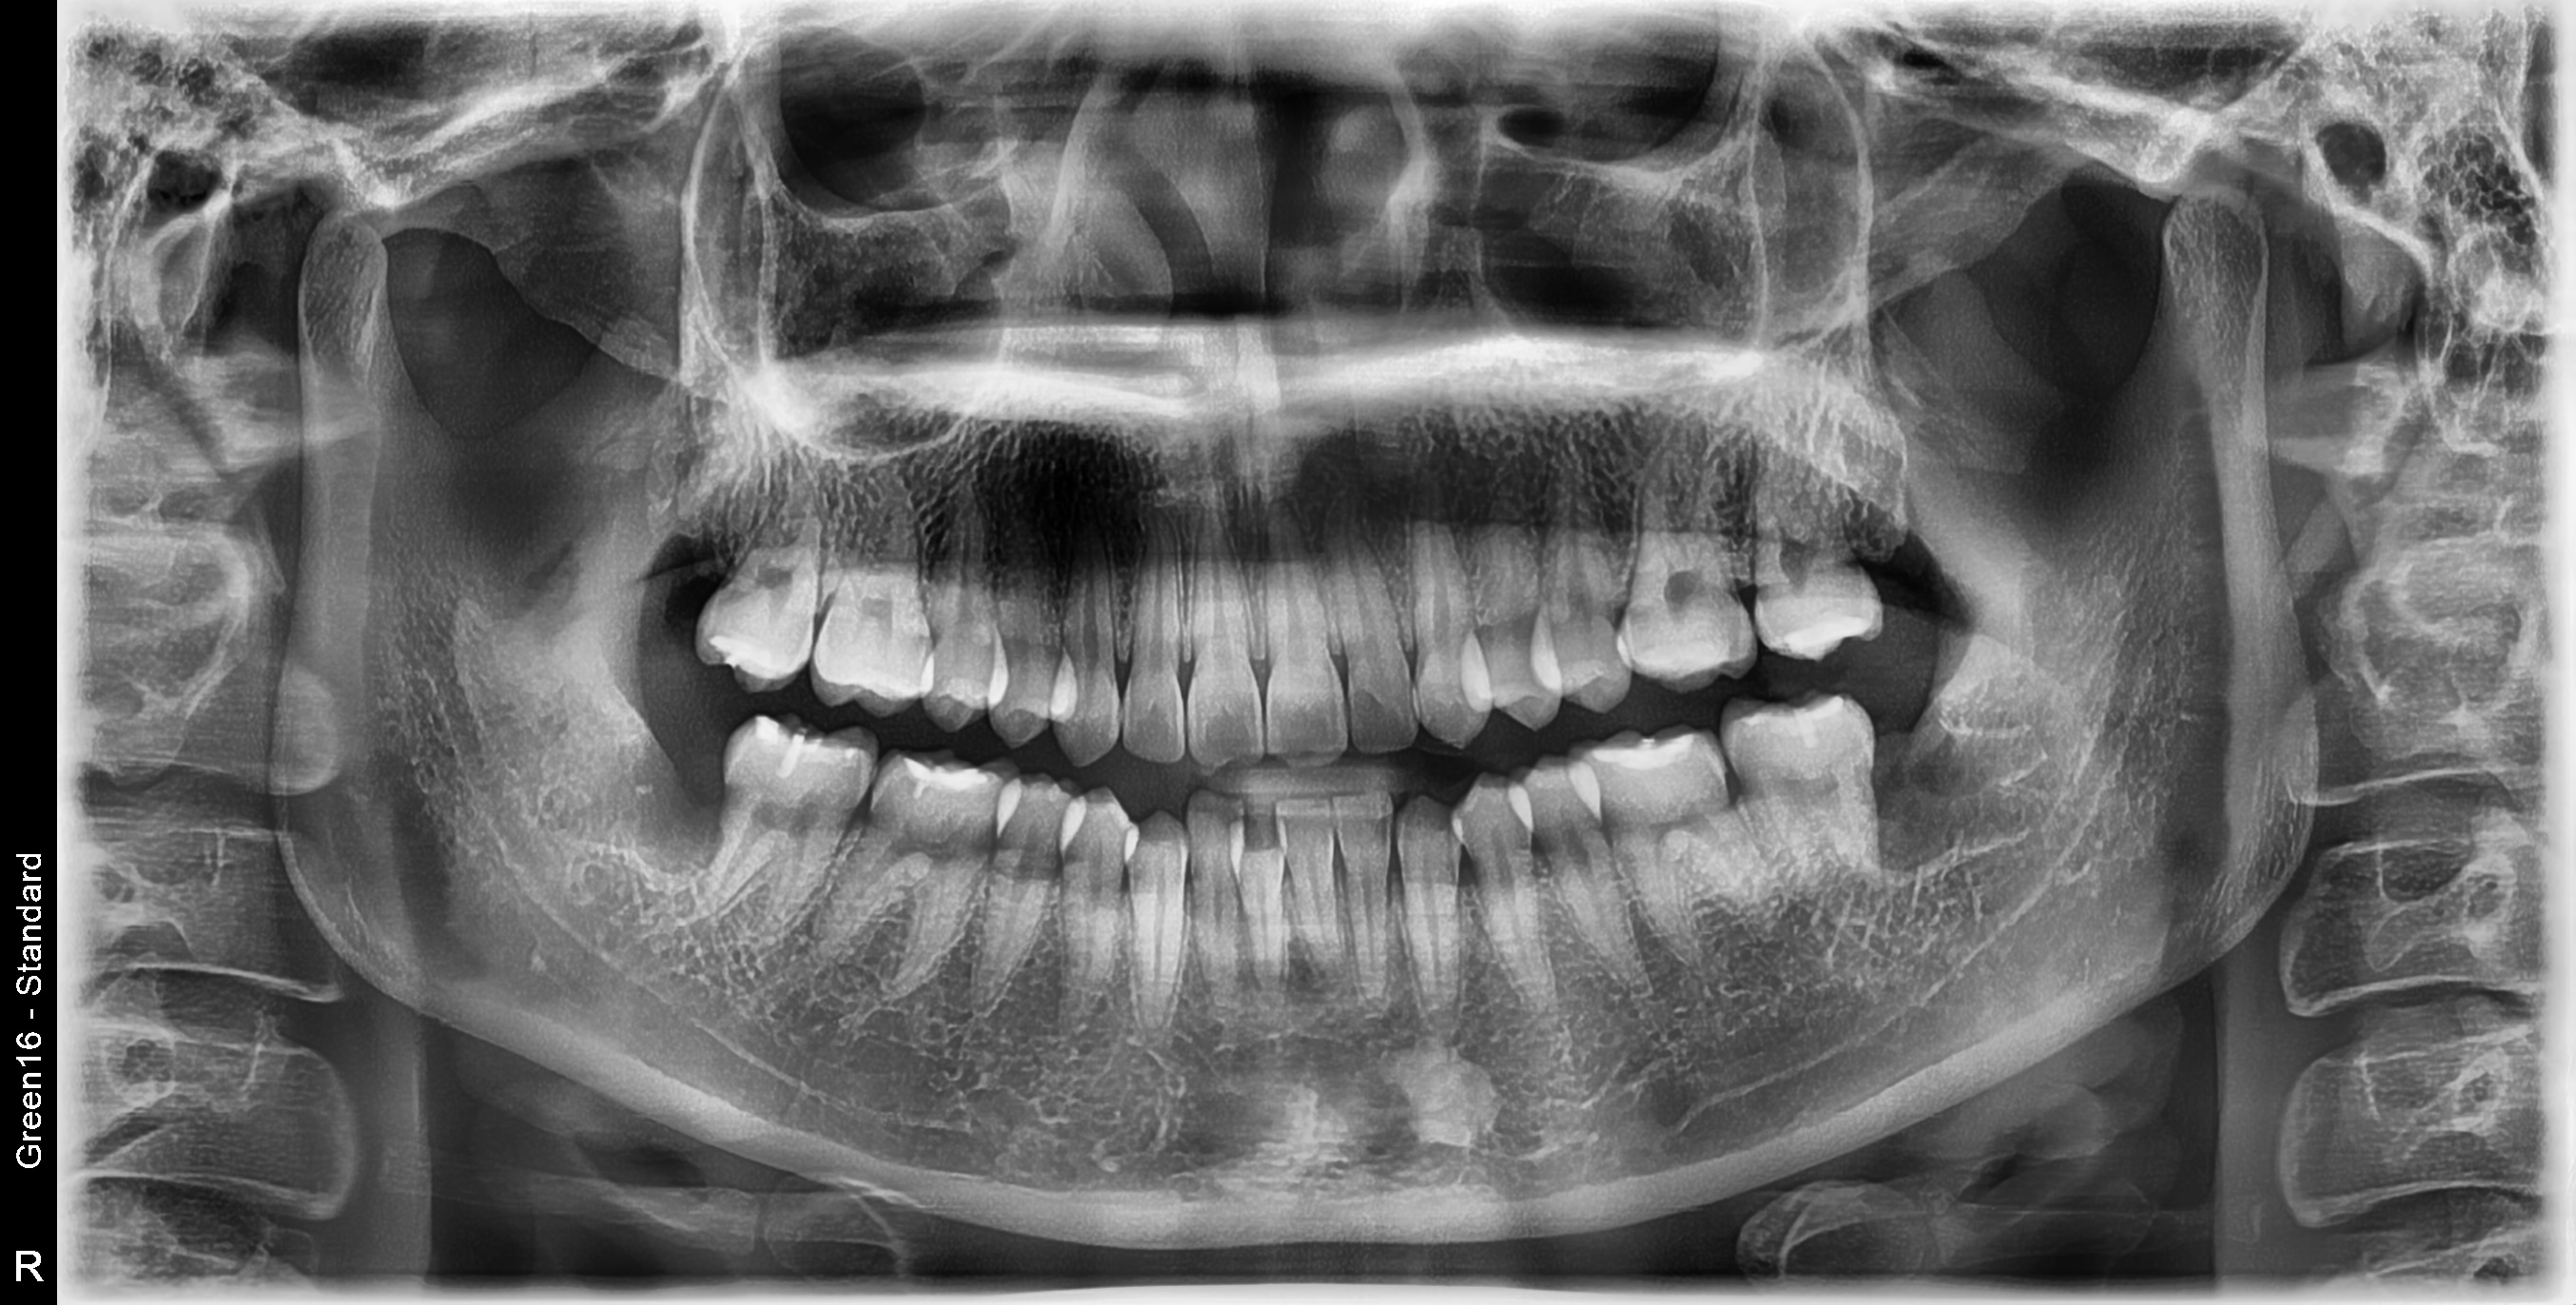

사랑니 완전매복치 발치 사례

전후사진

수술 전

수술 후